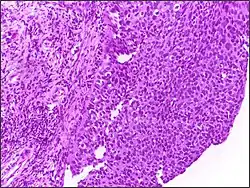

![]() | Squamous cell carcinoma of cervix | Invasive Squamous Carcinoma of the Cervix. Cold Knife Cone. | Category: Histopathology of squamous cell carcinoma of the cervix | Invasive squamous carcinoma of cervix |